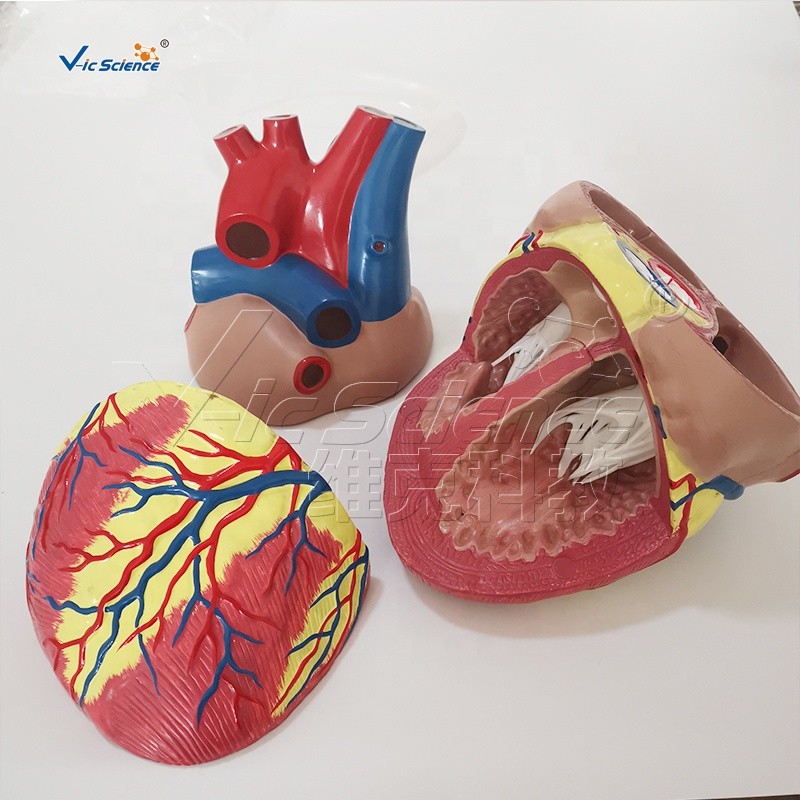

ขยายกายวิภาคหัวใจมนุษย์รุ่น 3 ชิ้นส่วน – Buy กายวิภาคหัวใจ,หัวใจ … หัวใจมนุษย์ การออกแบบรายละเอียด ภาพประกอบสต็อก – ดาวน์โหลดรูปภาพตอนนี้ …

ชีวิตพลาสติกกายวิภาคหัวใจมนุษย์รุ่น2ชิ้นส่วน – Buy การสอนรุ่น,Anatomy … ช็อคโกแลตรูปหัวใจ [ภาพวาดฟรี] | OkusanPix

ชีวิตพลาสติกกายวิภาคหัวใจมนุษย์รุ่น2ชิ้นส่วน – Buy การสอนรุ่น,Anatomy … ขนมช็อกโกแลตแท่ง ตรา โชกี้ โชกี้ 1 บาท แพ็ค 100 ชิ้น | Shopee Thailand

ขนมช็อกโกแลตแท่ง ตรา โชกี้ โชกี้ 1 บาท แพ็ค 100 ชิ้น | Shopee Thailand ชีวิตพลาสติกกายวิภาคหัวใจมนุษย์รุ่น2ชิ้นส่วน – Buy การสอนรุ่น,Anatomy …

ชีวิตพลาสติกกายวิภาคหัวใจมนุษย์รุ่น2ชิ้นส่วน – Buy การสอนรุ่น,Anatomy … รักสุดใจ! ช่อช็อกโกแลตให้เธอ รวมไอเดียช่อช็อกโกแลตสื่อรัก มอบให้แฟน

In-306 3d กายวิภาคศาสตร์หัวใจมนุษย์รูปแบบทางการแพทย์พลาสติกกายวิภาค … หัวใจมนุษย์ ภาพสต็อก – ดาวน์โหลดรูปภาพตอนนี้ – หัวใจ – อวัยวะภายใน, การ …

หัวใจวิทยาศาสตร์เรื่องกายวิภาคศาสตร์ทางการแพทย์หัวใจมนุษย์รุ่นขาย – Buy … หัวใจวิทยาศาสตร์เรื่องกายวิภาคศาสตร์ทางการแพทย์หัวใจมนุษย์รุ่นขาย – Buy …

หัวใจวิทยาศาสตร์เรื่องกายวิภาคศาสตร์ทางการแพทย์หัวใจมนุษย์รุ่นขาย – Buy … Anatomy หัวใจมนุษย์รุ่นพลาสติกทางการแพทย์กายวิภาคหัวใจจัมโบ้รุ่นอวัยวะ …

Anatomy หัวใจมนุษย์รุ่นพลาสติกทางการแพทย์กายวิภาคหัวใจจัมโบ้รุ่นอวัยวะ … รูปช็อกโกแลตหัวใจพร้อมน้ำเชื่อม PNG , วาเลนไทน์วัน, หัวใจ, วันแห่งความ …

3d Anatomy หัวใจมนุษย์รุ่นพลาสติกทางการแพทย์กายวิภาคหัวใจจัมโบ้รุ่น … หัวใจวิทยาศาสตร์เรื่องกายวิภาคศาสตร์ทางการแพทย์หัวใจมนุษย์รุ่นขาย – Buy …

หัวใจวิทยาศาสตร์เรื่องกายวิภาคศาสตร์ทางการแพทย์หัวใจมนุษย์รุ่นขาย – Buy … ส่งไว🚀24ชม. เจบีช็อกโกแลต รูปฟุตบอล เหรียญทอง เหรียญเงิน ทองแท่ง หัวใจ …

ส่งไว🚀24ชม. เจบีช็อกโกแลต รูปฟุตบอล เหรียญทอง เหรียญเงิน ทองแท่ง หัวใจ … Anatomy หัวใจมนุษย์รุ่นพลาสติกทางการแพทย์กายวิภาคหัวใจจัมโบ้รุ่นอวัยวะ …

Anatomy หัวใจมนุษย์รุ่นพลาสติกทางการแพทย์กายวิภาคหัวใจจัมโบ้รุ่นอวัยวะ … ภาพประกอบแบนเวกเตอร์หัวใจมนุษย์ขนาดใหญ่บนพื้นหลังสีขาว ภาพประกอบสต็อก …

หัวใจมนุษย์กายวิภาครุ่นวิทยาศาสตร์การแพทย์รูปแบบการสอน ห้องหัวใจมนุษย์: คำอธิบายโครงสร้างหน้าที่และประเภท

หุ่นจำลองหัวใจมนุษย์ 3d มนุษย์กายวิภาครุ่นหัวใจมนุษย์สำหรับซัพพลายเออร์แบบครบวงจรวิทยาศาสตร์ …

3d มนุษย์กายวิภาครุ่นหัวใจมนุษย์สำหรับซัพพลายเออร์แบบครบวงจรวิทยาศาสตร์ … 3d Anatomy หัวใจมนุษย์รุ่นพลาสติกทางการแพทย์กายวิภาคหัวใจจัมโบ้รุ่น …

3d Anatomy หัวใจมนุษย์รุ่นพลาสติกทางการแพทย์กายวิภาคหัวใจจัมโบ้รุ่น … อวัยวะหัวใจของมนุษย์ | องค์ประกอบกราฟฟิก แบบ PSD ดาวน์โหลดฟรี – Pikbest

หัวใจมนุษย์กายวิภาครุ่นวิทยาศาสตร์การแพทย์รูปแบบการสอน 15 Porch ช็อกโกแลต Fudge แม่พิมพ์ซิลิโคนหัวใจรูปเค้กช็อกโกแลตตกแต่ง DIY …

อุปกรณ์การศึกษากายวิภาคศาสตร์รุ่นหัวใจมนุษย์รุ่นสำหรับโรงเรียนขนาดชีวิต … วิธีทำ “นามะช็อกโกแลต” ของฝากยอดฮิตจากญี่ปุ่น อร่อยหรูดูแพง แต่ทำง่าย …

โรงงานโดยตรงขาย Anatomy หัวใจมนุษย์การฝึกอบรมชุดอวัยวะภายในรุ่น – Buy …